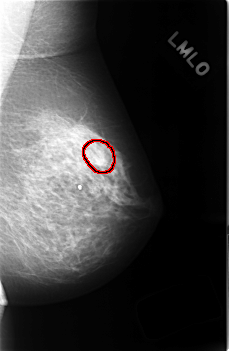

C_0434_1.LEFT_MLO

LEFT_MLO LINES 4552 PIXELS_PER_LINE 2976 BITS_PER_PIXEL 12 RESOLUTION 50 OVERLAY

FILE: C_0434_1.LEFT_MLO.OVERLAY

TOTAL_ABNORMALITIES 1

ABNORMALITY 1

LESION_TYPE MASS SHAPE IRREGULAR MARGINS SPICULATED

ASSESSMENT 3

SUBTLETY 3

PATHOLOGY BENIGN_WITHOUT_CALLBACK

TOTAL_OUTLINES 1

BOUNDARY